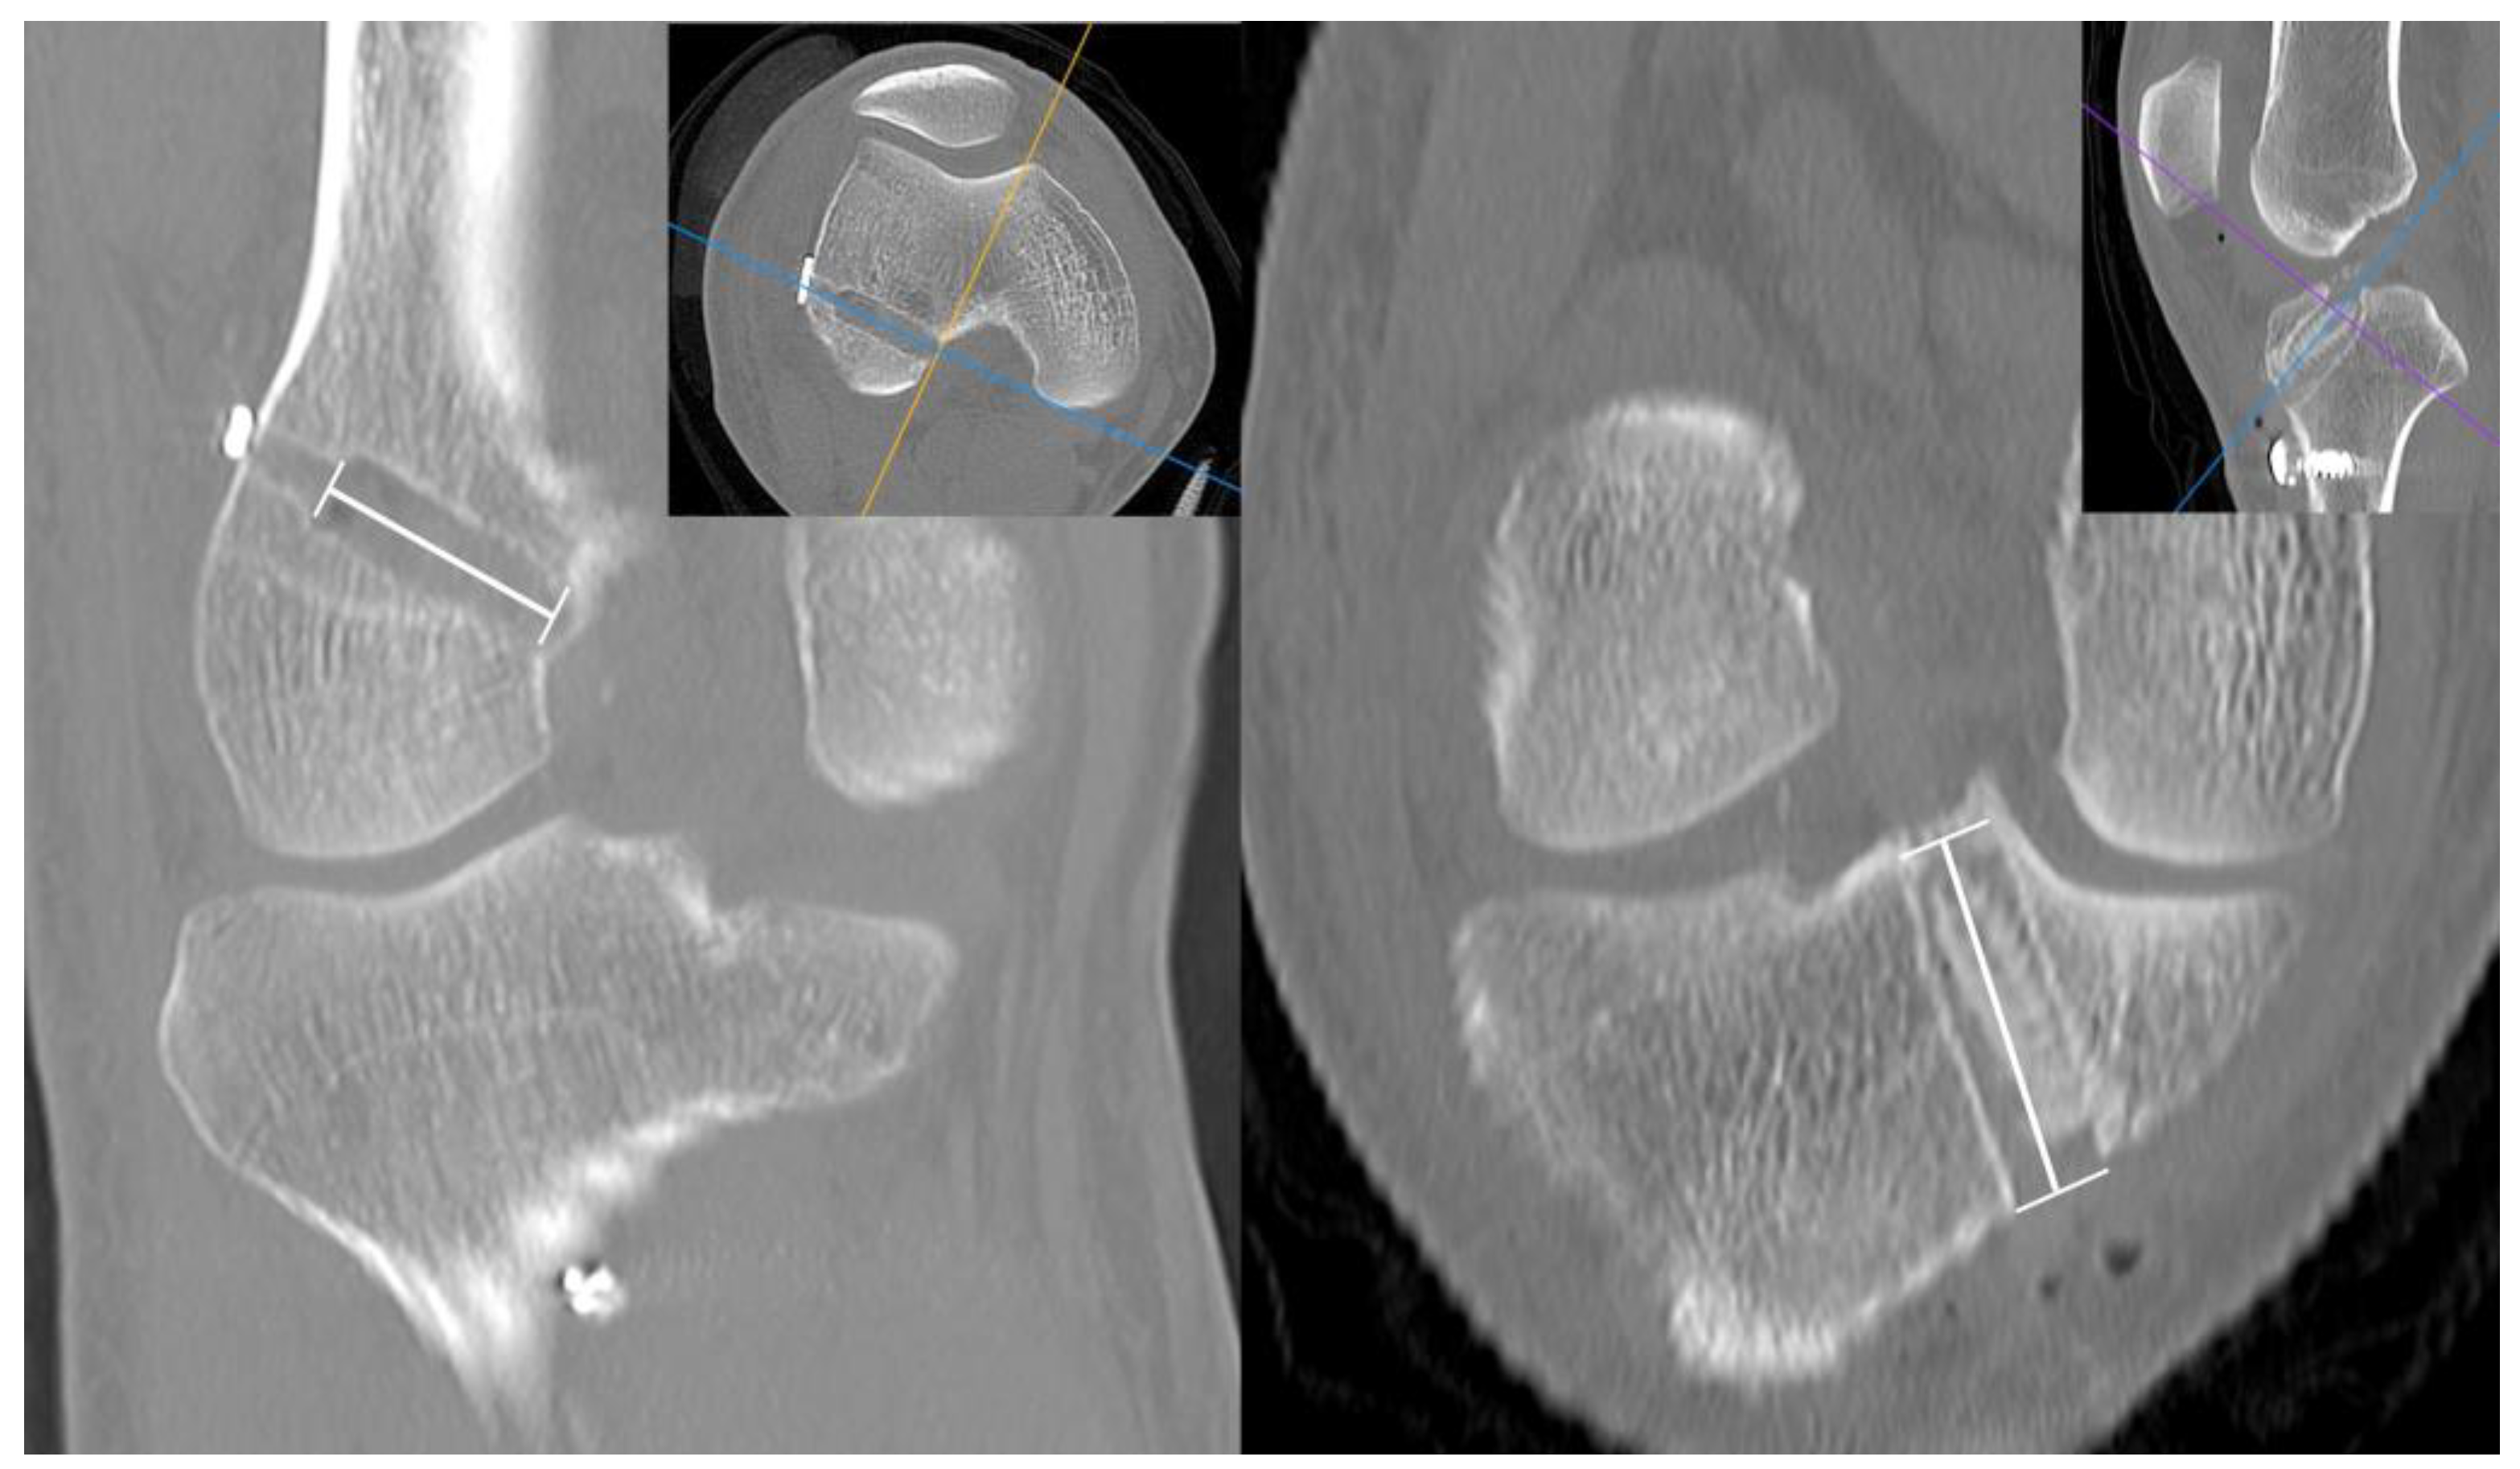

Computed tomography (CT) was performed 3 days postoperatively. Three-dimensional CT images were used to measure the femoral and tibial tunnel positions. The center of the femoral and tibial tunnel apertures was measured on the standardizeds grid system as described previously [20]. In terms of the femoral tunnel, the higher limit of the grid was located on the femoral notch roof, and the anterior, posterior, distal, and proximal sides of the grid were located on the articular cartilage margin. The height and depth of the femoral tunnel were measured. With respect to the tibial center, a rectangular grid was located at each end edge of the tibial plateau. The AP and mediolateral (ML) tibial tunnel positions were then calculated (Figure 5).

Figure 5.

The center of the femoral and tibial tunnel (red dots) was calculated on 3-dimensional CT with the quadrant method. The height and depths of femoral tunnel position and anteroposterior and mediolateral tibial tunnel position were measured.